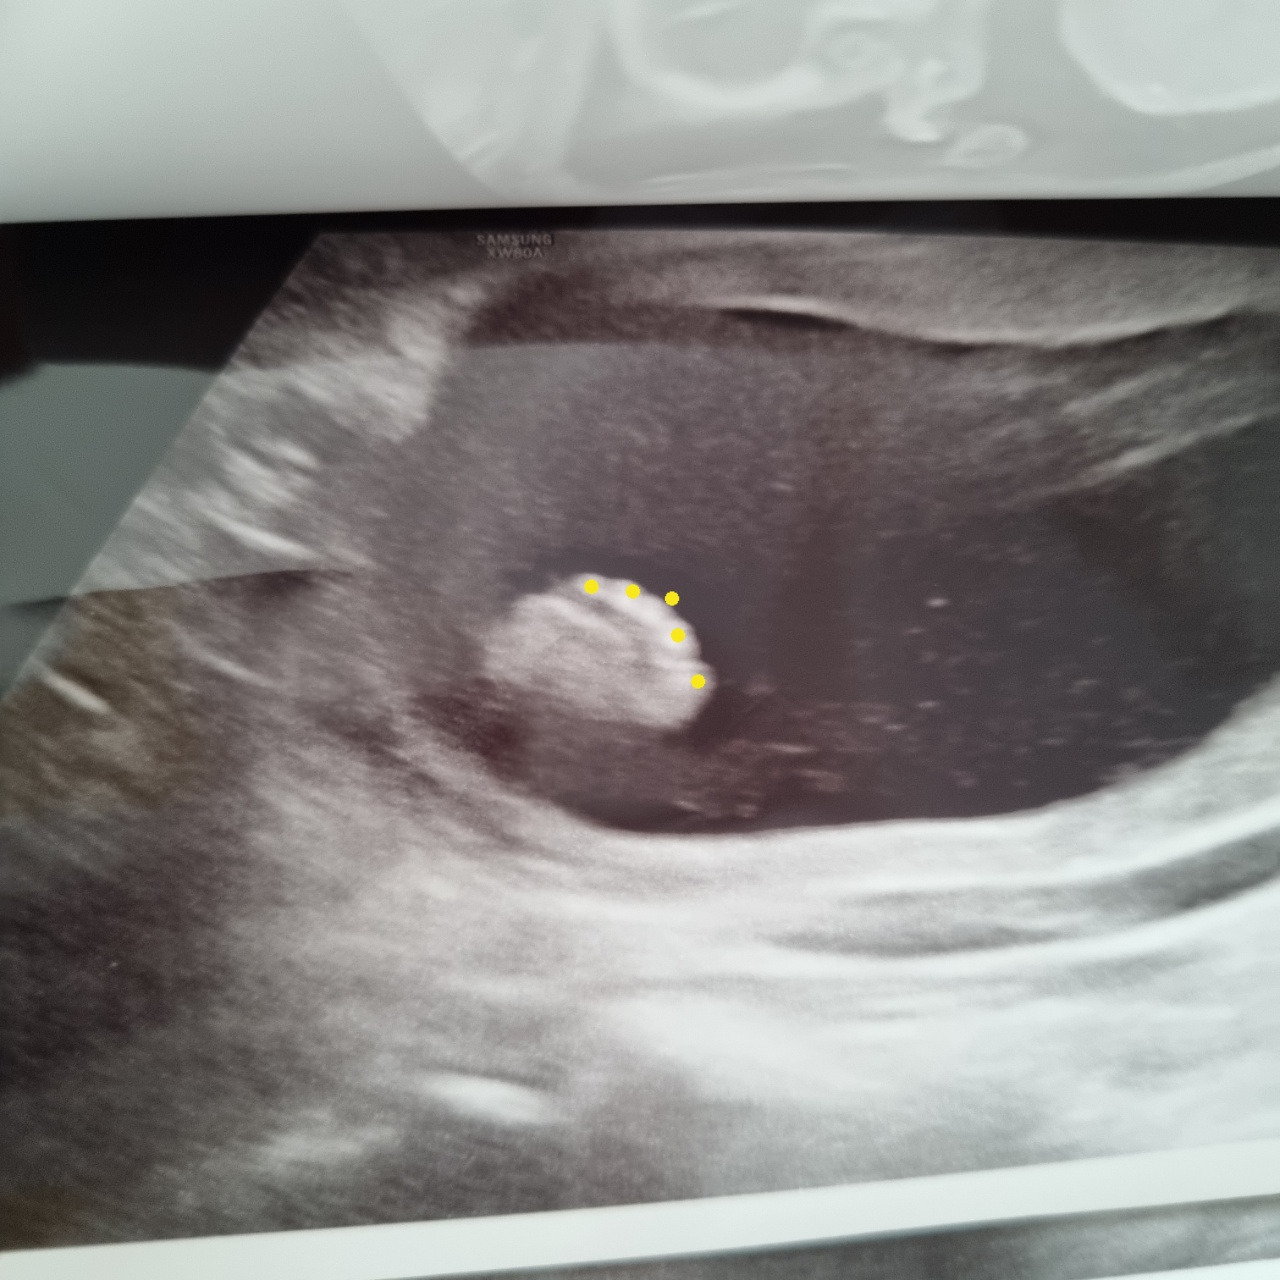

원래 다음 산부인과 검진일은 11월이었는데 아내는 아가가 너무 보고 싶다며 이번 주에 초음파를 보고 왔다. 손가락도 5개, 발가락도 5개 아주 예쁘게 잘 자라고 있다. 저 작은 손가락에는 지문도 생긴다고 한다. 이제 정말 디테일한 부분까지 같이 자라고 있는 셈이다. 아가는 저번 초음파 때에도 다리를 꼬고 있었는데, 이번에도 꼰 채로 놀고 있었다. 아무래도 다리 꼰 자세가 편한 모양이다.